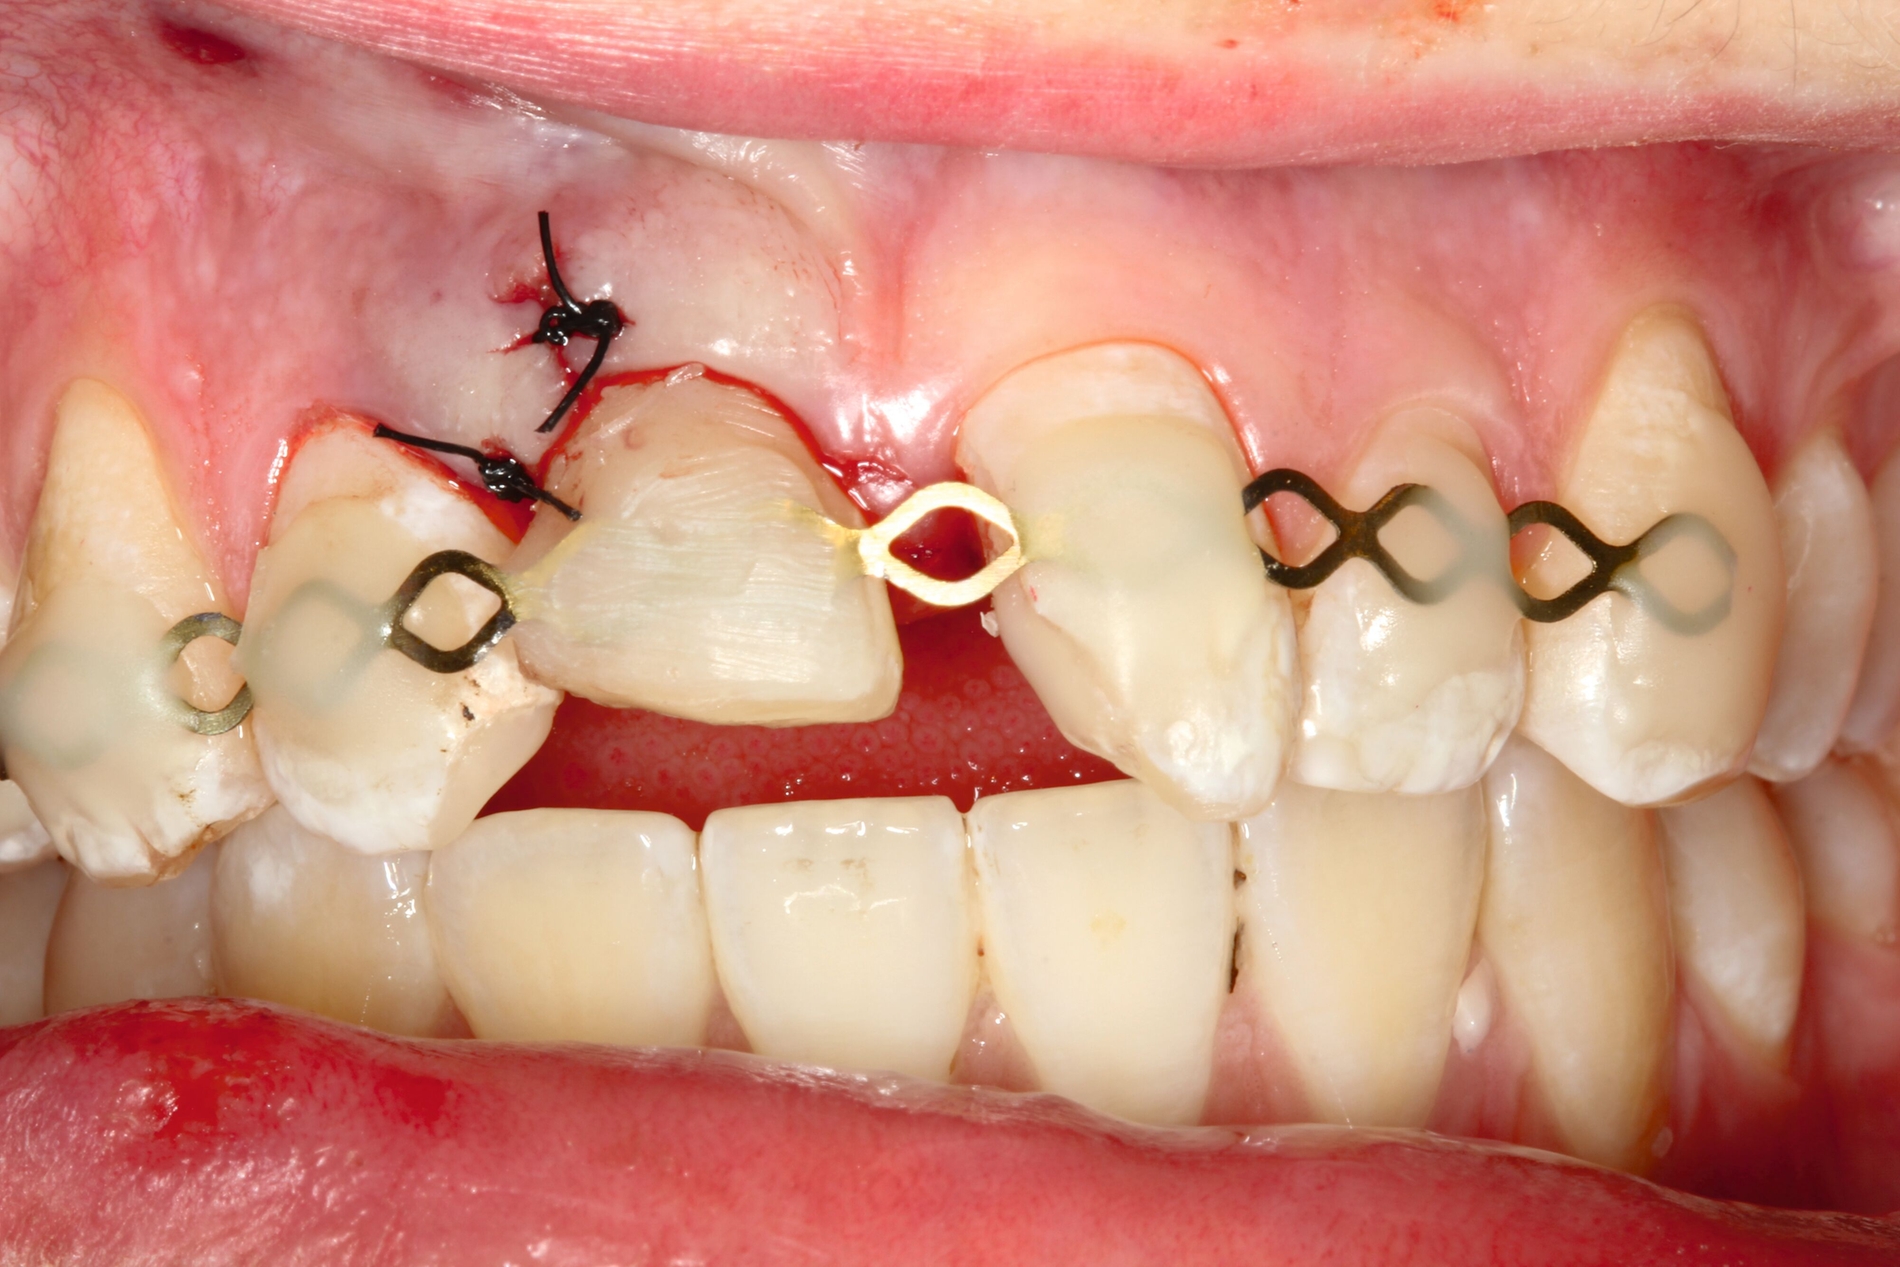

Im Fall von Kronen-Wurzel-Frakturen ist die adhäsive Fragmentbefestigung auch empfehlenswert, sofern die Fraktur suprakrestal verläuft und durch Elektrotomie oder Aufklappung suffiziente Bedingungen für adhäsive Maßnahmen geschaffen werden können. Gleichzeitig müssen zusätzliche kleinere Frakturen, die sich oftmals im palatinal-zervikalen Bereich der Wurzel befinden, ausgeschlossen werden. Die Datenlage zur klinischen Bewährung ist überschaubar. Studien zeigen sehr gute Ergebnisse innerhalb der ersten zwei Jahre [Eichelsbacher et al., 2009], aber auch erhöhte Komplikationsraten und einen negativen Einfluss auf die parodontale Gesundheit der versorgten Zähne nach einem Beobachtungszeitraum von acht Jahren [Soliman et al., 2020].

Alternativ dazu bietet sich die Koronalverlagerung der Defektgrenze mit gleichzeitiger Wiederherstellung der biologischen Breite durch eine kieferorthopädische (siehe Teil 5 der Fortbildung „Dentales Trauma“: Kieferorthopädische Aspekte) oder die chirurgische Extrusion an (Abbildung 2).